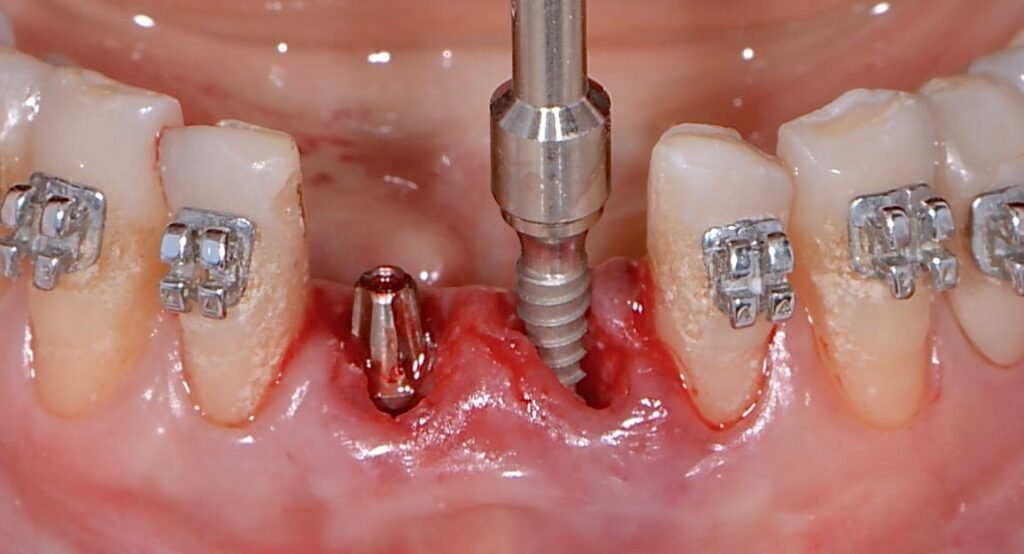

2º – Fresagem para implante imediato;

3º – Instalação de uma membrana de reabsorção lenta entre o osso e o retalho descolado;

4º – Reconstrução da parede vestibular com enxerto ósseo a base de hidroxiapatita associada a fibra colágena (Extra Graft XG-13);

5º – Instalação do implante;

6º – Preenchimento de GAP residual se houver.